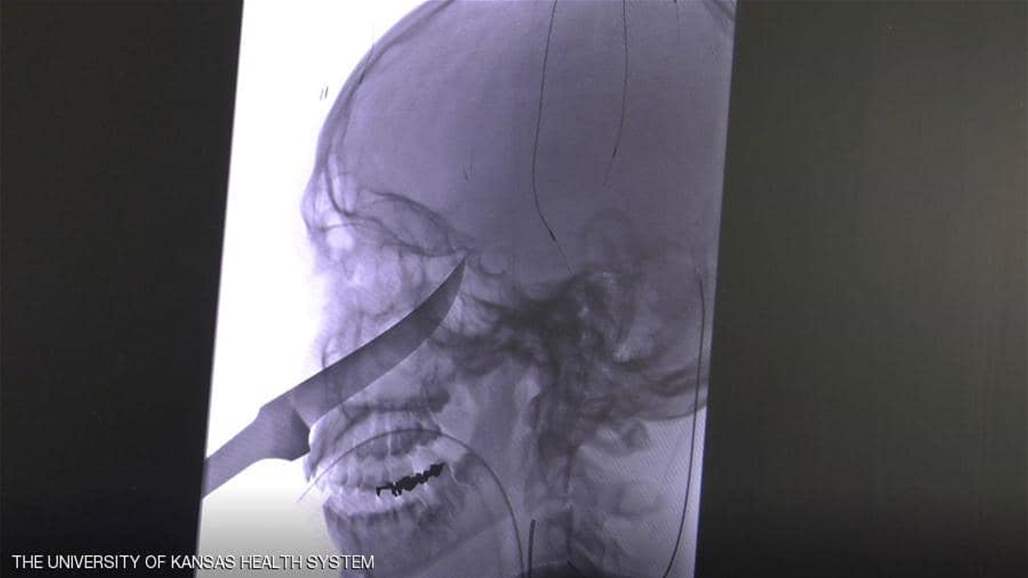

سكين حاد يدخل في جمجمة مراهق، وهكذا نجا...

نجح فريق طبي أميركي في إنقاذ حياة مراهق من ولاية كانساس، تم نقله إلى المستشفى بينما كان سكين طوله 25 سنتيمترا يخرج من جمجمته.

وفي مستشفى ميرسي للأطفال في كانساس، هرع المسعفون حيث رأى الأطباء احتمال تلف الشريان السباتي في دماغه، الأمر الذي كان سيؤدي إلى الإصابة بالسكتة الدماغية أو أضرار جسيمة، فقرر الأطباء نقله إلى نظام

وهناك تم تخصيص فريق طبي تمكن في أقل 24 ساعة من إنقاذ إيلي، الذي يخضع حالياً للعلاج بمجموعة من المضادات الحيوية واللقاح ضد الكزاز (التيتانوس)، فيما أمره الأطباء بالابتعاد عن أي أشياء حادة.